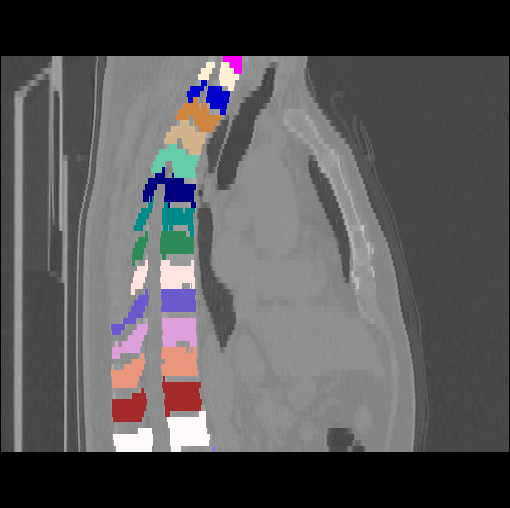

Images

GT

Predictions

We calculate the two metrics of each vertebra, and the results are reported in Table 2. On the one hand, our experimental results are close to those reported in reference (Sekuboyina et al., 2020) with the same model (nnUnet), verifying the high quality of our annotations. On the other hand, Table 2 shows it is difficult to segment the diseased vertebrae (the DSC of L6 is almost 0). Specifically, the existence of L6 confuses the model, resulting in prediction dislocations (see the last row in Fig. 4). Thus, our labeled dataset, which contains many L6 cases, is very valuable for the diseased vertebrae segmentation (we have stated those cases that are hard for annotation in the readme.txt file). Table 2 illustrates that the model trained with our annotations can achieve good performance on our CTSpine1K dataset but a much worse performance on the VerSe Challenge datasets, which explains there is an obvious domain gap between our annotated dataset and the public dataset. We infer the reason is that the COlONOG dataset is based on an empty stomach and colon, confusing the deep learning model by the changes of air content in the abdomen (see Fig. 3). Therefore, our annotations are a good complement to the existing datasets.

3.2.2 Qualitative results.

Some visualization results are presented in Fig. 4, where we can observe that the baseline model can achieve excellent segmentation results. Nevertheless, some failed predictions occur when spinal diseases exist, especially sacral lumbarization and lumbar sacralization. Besides, the image’s resolution of Z direction is closely related to the results, and a lower resolution leads to worse results. Maintaining a reasonable performance for a low resolution is a research challenge. Image superresolution (Peng et al., 2020) might be worth exploring.